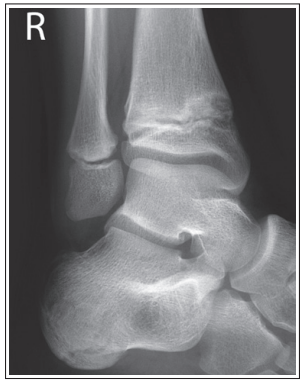

What are the issues with this mortise ankle?

Medial mortise is closed, and anterior tibial margin has been projected proximal to the posterior margin

Distal tibia has been elevated